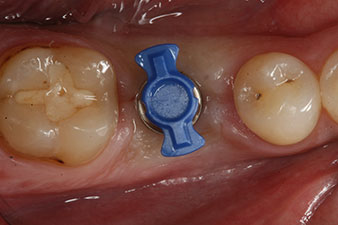

Fig. 1: Initial clinical situation after healing of extraction alveolus 36: The bone base is wide and there is sufficient keratinized gingiva.

SmartPeg

Fig. 4: SmartPeg measuring posts screwed on to measure the implant stability quotients with the integrated W&H Osstell ISQ module.

The torque used for the machine-driven placement was 43 Ncm. In addition, after screwing a measuring post (SmartPeg) specially matched to the implant, the ISQ value was measured with the probe of the W&H Osstell ISQ module.